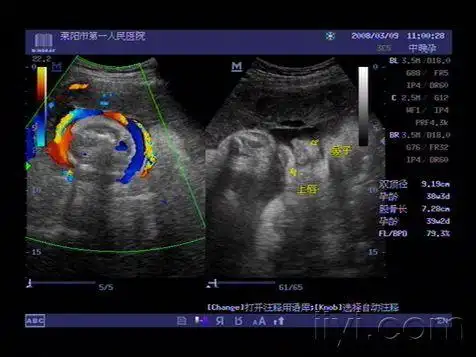

胎儿脐带绕颈及唇部欣赏 - 超声医学讨论版 - 爱爱医医学论坛